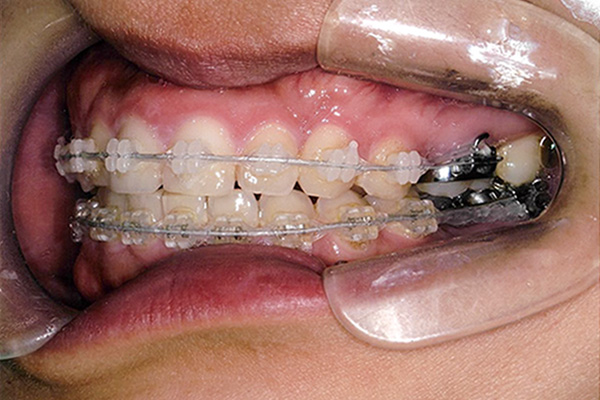

3ヶ月後

10ヶ月後

24ヶ月後

42ヶ月後